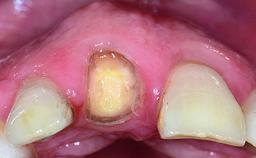

A healthy 38-year-old male patient was referred for replacement of a failing tooth-supported cantilever fixed dental prosthesis on teeth 11 and 21. The patient reported a history of trauma at 13 years of age that had resulted in the subsequent loss of tooth 11, as well as endodontic treatment of the adjacent abutment tooth 21. A metal-ceramic cantilever fixed dental prosthesis replacing tooth 11 had been provided by his general dentist several years after the loss of the tooth, with tooth 21 as the sole abutment. At the time of initial presentation, this restoration had been in service for over 20 years.